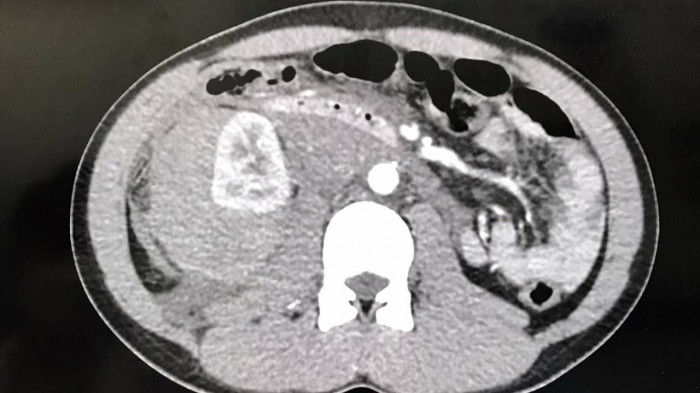

Qua thăm khám và thực hiện các cận lâm sàng cần thiết, các bác sĩ chẩn đoán người bệnh bị chấn thương thận phải độ IV (AAST) gây xuất huyết nội và vỡ gan hạ phân thùy VII độ I. Người bệnh được tiến hành cấp cứu, điều trị nội khoa tích cực, theo dõi sát mạch, huyết áp và tình trạng bụng.

Ảnh chụp CT Scanner trước khi can thiệp nội mạch.